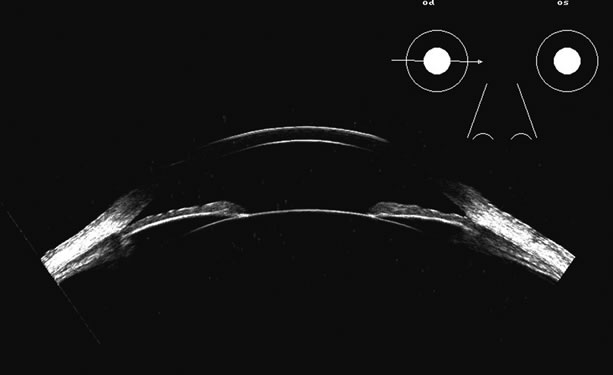

in the 50 MHz range for examining this region.5–7 Lens position, presence, and integrity can be shown most easily with immersion ultrasound, since the proximity of these structures to the transducer in contact techniques makes them difficult to display. Immersion or a water standoff makes it possible to visualize the anterior segment by moving the “noise” of the main bang of the transducer forward, away from the structures of interest and the focal zone onto this area.8 The lens is a “specular” reflector which, like the cornea, is a smooth, highly reflective surface. Whereas specular reflectors, such as the lens, may deflect most acoustic energy away from the transducer when insonified at an oblique angle, “diffuse” reflectors, such as blood-covered membranes, are more easily discerned on B-scan. Blood enhances lens boundaries; that is, it converts the specular reflective surface to a diffuse reflective surface, making the entire outline of the surface more easily seen, even at regions angled so they would otherwise deflect the returning echoes away from the transducer and not be identifiable. The posterior capsule is concave and thus perpendicular to the beam over much of the arc of sector B-scanning, thus making it always easy to identify. The lens outline should be smooth and unbroken (Fig. 1); a damaged lens often is cataractous and has internal echoes as well as interrupted surface echoes.9 Kinetic scanning, that is, real-time scanning while the patient moves his or her eye, can be used to check for mobility of the lens in dislocated or partially dislocated lenses. The four main areas of interest in the posterior chamber to the ocular surgeon are (1) iris and ciliary body tumors, (2) intraocular foreign bodies and trauma that may involve the lens, (3) intraocular lens placement and position that may cause irritation or decreased vision, and (4) hypotony with separation of the ciliary body from the sclera.10 Examples of a retroiridal cyst and a tumor are shown in Figures 2 and 3. Intraocular lens displacement, particularly erosion of haptics that may produce bleeding, is a commonly seen problem. An intraocular lens with a folded haptic is seen in Figure 4 and a retro displaced haptic is shown in Figure 5.